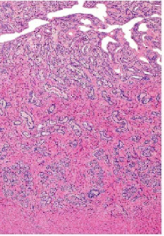

What organ is in the image provided and what phase of the estrous cycle is it in?

uterus in estrus